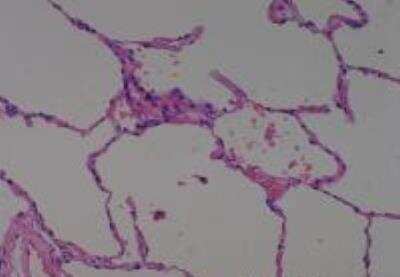

Hematoxylin & Eosin Stain: Human Common Tissue MicroArray (Normal Adjacent) [NBP2-30215] - 103. Stomach